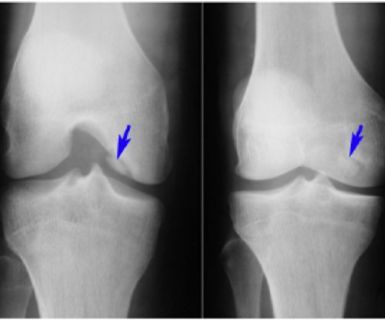

Desde pequeña sufría de una curvatura en las piernas y mis rodillas siempre estaban torcidas. Cada paso era incómodo, y me daba vergüenza usar ropa que dejara ver mis piernas. Los médicos decían que solo con cirugía podría corregirlo, pero me aterraba la idea. Encontré este método y decidí intentarlo. ¡Fue lo mejor que pude hacer! Con dedicación y paciencia, mis piernas se alinearon, y el cambio es evidente. Incluso adjunto mis fotos del antes y después porque yo misma aún me sorprendo al ver el resultado. ¡Es increíble cómo ha cambiado mi vida!